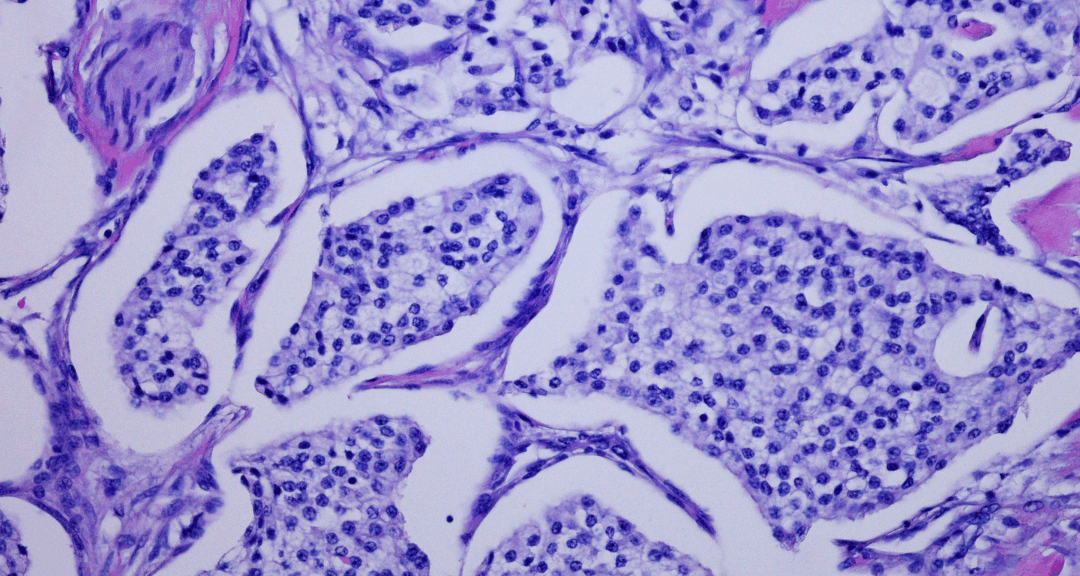

Le cancer de la prostate résistant à la castration métastatique a connu des avancées grâce aux inhibiteurs de la voie des récepteurs androgéniques (ARPIs), qui améliorent la survie globale. Cependant, ces traitements sont associés à une fréquence accrue de cancer neuroendocrine lié au traitement. L’objectif principal de cette étude a été de quantifier la proportion de cas d’adénocarcinome prostatique qui évoluent vers la forme neuroendrocrine après un traitement par ARPI. L’étude a révélé que parmi 938 patients issus de huit études, 171 ont été diagnostiqués avec cancer neuroendrocrine, principalement par pathologie. La fréquence globale après traitement par ARPI a été estimée à 16 %.